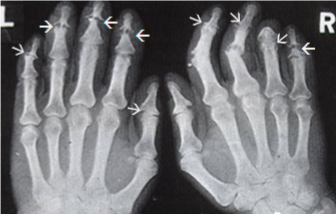

Rheumatoid Arthritis

Juxta-articular erosions (lysis of bone/osteopenia)

Joint ankylosis

Juxta-articular bone erosions

Late dislocations

Ulnar deviation